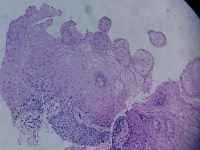

贲门活检

性别

男

年龄

68岁

上腹部不适,贲门可见不规则病灶,触之易出血

贲门粘膜

大体所见

腺癌